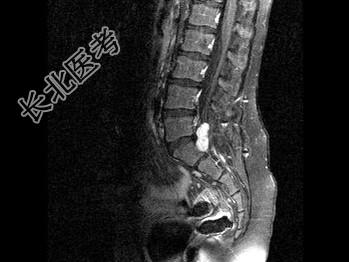

- 单项选择题男,8岁, 左髋疼痛,跛行1月余, 结合MRI检查,最可能的诊断是 ( )

A、骶部神经鞘瘤

B、室管膜瘤

C、神经纤维瘤

D、脊膜瘤

E、脊髓空洞症